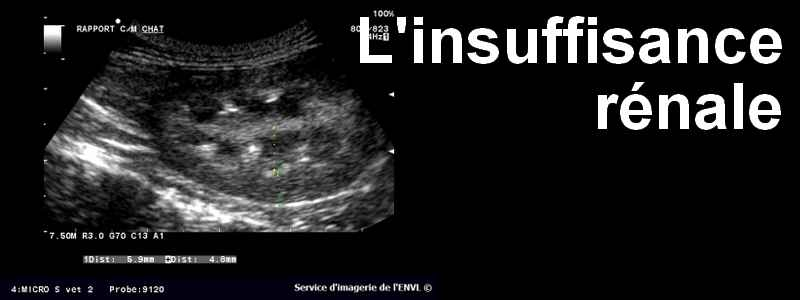

Vincent Ouédraogo, jeune enseignant a été diagnostiqué insuffisant rénal en 2020. Chaque séance de dialyse lui coûte 95000F CFA. « Je devais le faire au moins 2 à 3 fois par semaine. J’ai dû suivre la dialyse jusqu’à un certain moment où je n’en pouvais plus », dit-il. Comme Vincent, plusieurs malades d’insuffisance rénale manquent de moyens financiers pour suivre les soins.